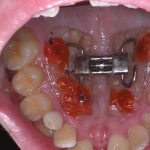

Sopravvivenza di Impianti Core-X® posizionati con chirurgia driver guidata

In questo articolo viene effettuata un’analisi retrospettiva per verificare la sopravvivenza di Impianti Core-X® posizionati con chirurgia driver guidata, con un follow up minimo...